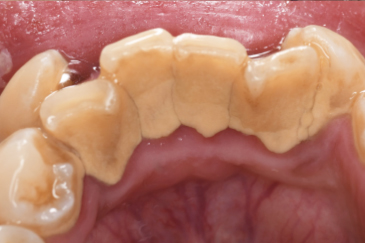

※30代・男性:歯並びが悪いこともあり、下前歯の裏に歯石の付きやすい方

特に下の前歯の舌側(裏側)は、唾液の影響で歯石がつきやすいだけでなく、自分では見えにくい部位であるために歯ブラシが当てにくく、どんなにしっかり磨いていても数ヵ月ごとのクリーニングが必要なほど歯石がつきやすい部位といわれています。